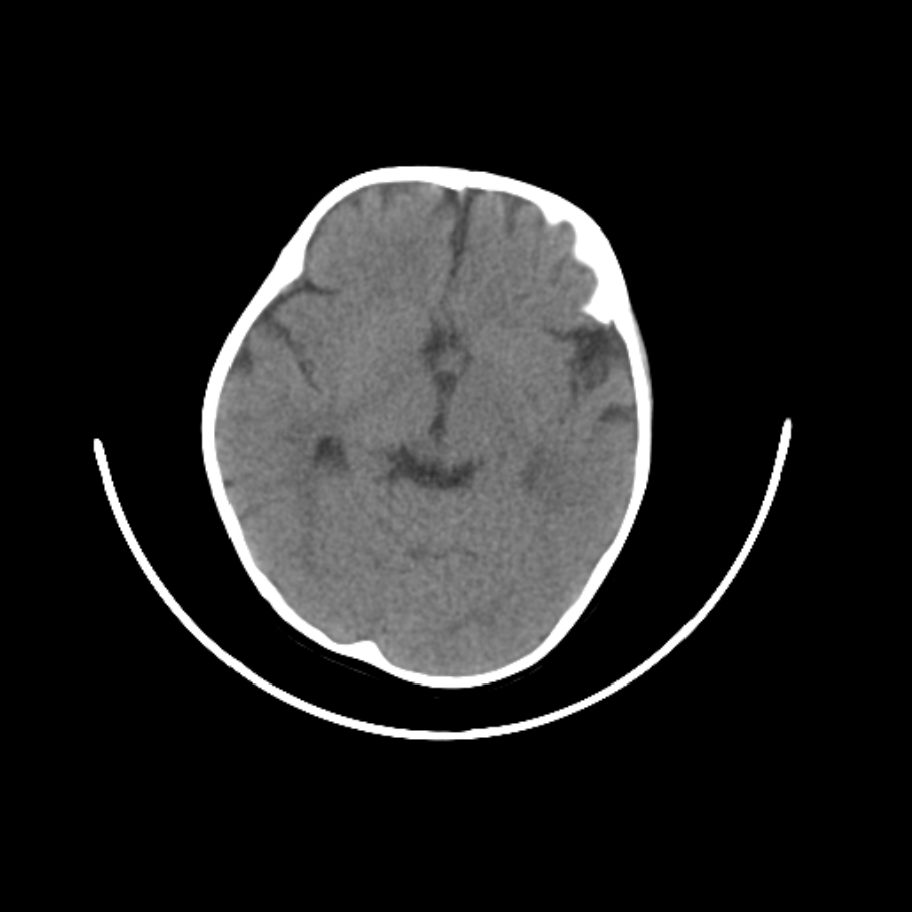

以下是引用随光逐影在2009-4-8 7:51:00的发言:[br]1)透明隔缺如(视-隔发育不良?)。2)右侧脑裂畸形。3)右侧幕上半球脑萎缩。